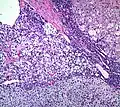

Zona fasciculata versus adrenocortical adenoma. An adrenocortical adenoma typically has mild changes in comparison, including larger cells with larger and more pleomorphic nuclei with more coarse chromatin. H&E stain.

The microscopic histopathology analysis of the tissue samples obtained from the adrenal cortex of individuals presenting with adenoma-associated symptoms such as primary aldestronism (PA) indicates that adenoma cells are relatively larger with different cytoplasm, and increased variation in nuclear size. This indication is based on comparison between the healthy (normal) and affected (adenoma-associated) adrenal cortex tissue samples.